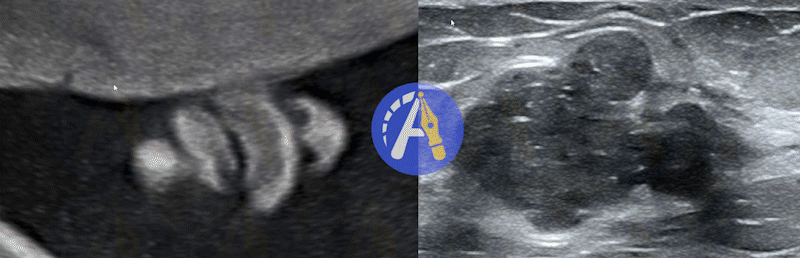

多模态影像互补标注

单一的影像模态使医生对病灶的定位和标注存在明显局限性。通过多模态信息的同步观察与互补使用,有利于医生准确标注病灶,如结合MRI中的T1与T2影像、多模态的超声影像、PET和CT影像、不同荧光染色的细胞涂片影像等。Pair提供的多模态影像互补标注功能可在标注过程同步显示不同模态的影像,降低医生对目标区域的定位和轮廓勾画的不确定度,有效帮助医生进行识别和标注。Pair提供的多模态标注功能可兼容二维、视频、三维和病理图像。